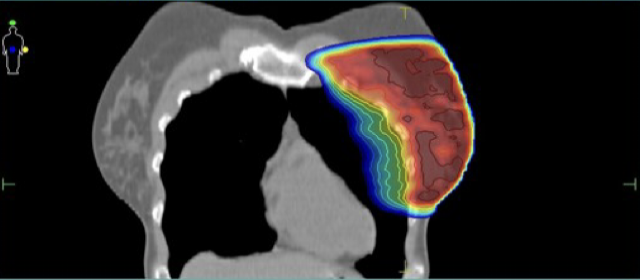

Κατανομή δόσης με την τεχνική ABC

Ελαχιστοποίηση δόσης στην καρδιά και τον πνεύμονα